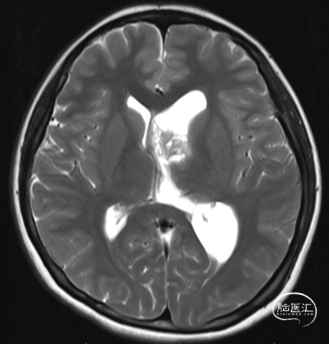

现病史:患者1年前无诱因出现间断头痛,不伴随恶心呕吐等,起初未在意。1个月前上述症状加重,伴随恶心,在当地医院检查CT发现左侧脑室内占位病变,左侧脑室扩大。家人为求彻底治疗来我院,门诊以“1. 左侧脑室内占位;2. 左侧脑室积水”为诊断收入我科。

T2

头部磁共振提示:左侧侧脑占位病变,增强后不染色